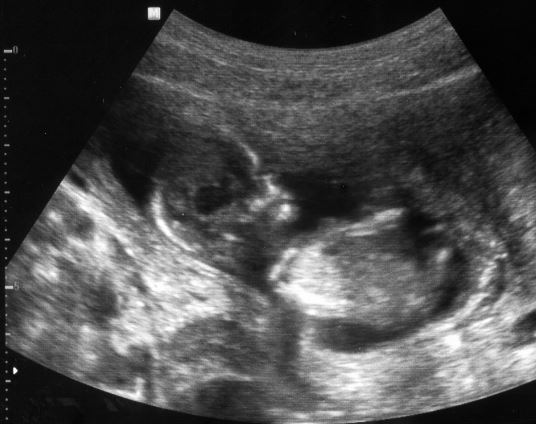

Goga super zdjatko. Gebe twarz zaslonil, ale nogi rozlozyl :-)

Mojeboje super ze wszystko jest w porzadku. I zdjecia tez super, szczegolnie to z raczka.